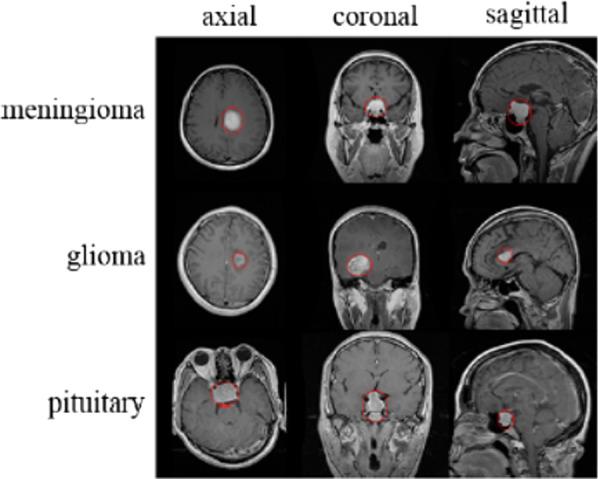

Detecting brain tumors in their early stages is crucial. Brain tumors are classified by biopsy, which can only be performed through definitive brain surgery. Computational intelligence-oriented techniques can help physicians identify and classify brain tumors. Herein, we proposed two deep learning methods and several machine learning approaches for diagnosing three types of tumor, i.e., glioma, meningioma, and pituitary gland tumors, as well as healthy brains without tumors, using magnetic resonance brain images to enable physicians to detect with high accuracy tumors in early stages.

A dataset containing 3264 Magnetic Resonance Imaging (MRI) brain images comprising images of glioma, meningioma, pituitary gland tumors, and healthy brains were used in this study. First, preprocessing and augmentation algorithms were applied to MRI brain images. Next, we developed a new 2D Convolutional Neural Network (CNN) and a convolutional auto-encoder network, both of which were already trained by our assigned hyperparameters. Then 2D CNN includes several convolution layers; all layers in this hierarchical network have a 2*2 kernel function. This network consists of eight convolutional and four pooling layers, and after all convolution layers, batch-normalization layers were applied. The modified auto-encoder network includes a convolutional auto-encoder network and a convolutional network for classification that uses the last output encoder layer of the first part. Furthermore, six machine-learning techniques that were applied to classify brain tumors were also compared in this study.

早期发现脑瘤至关重要。脑瘤通过活检进行分类,而活检只能通过明确的脑部手术进行。面向计算智能的技术可以帮助医生识别和分类脑瘤。在这里,我们提出了两种深度学习方法和几种机器学习方法,用于使用磁共振脑图像诊断三种类型的肿瘤,即胶质瘤、脑膜瘤和垂体瘤,以及没有肿瘤的健康大脑,使医生能够高精度地检测早期肿瘤。

本研究使用了包含 3264 个磁共振成像 (MRI) 脑图像的数据集,其中包括胶质瘤、脑膜瘤、垂体瘤和健康大脑的图像。首先,对 MRI 脑图像应用预处理和增强算法。接下来,我们开发了一个新的 2D 卷积神经网络 (CNN) 和一个卷积自动编码器网络,这两个网络都由我们指定的超参数进行了训练。然后,2D CNN 包括几个卷积层;这个分层网络中的所有层都有一个 2*2 的核函数。该网络由八个卷积层和四个池化层组成,在所有卷积层之后,应用批量归一化层。修改后的自动编码器网络包括一个卷积自动编码器网络和一个使用第一部分最后输出编码器层的分类卷积网络。此外,本研究还比较了六种应用于分类脑瘤的机器学习技术。